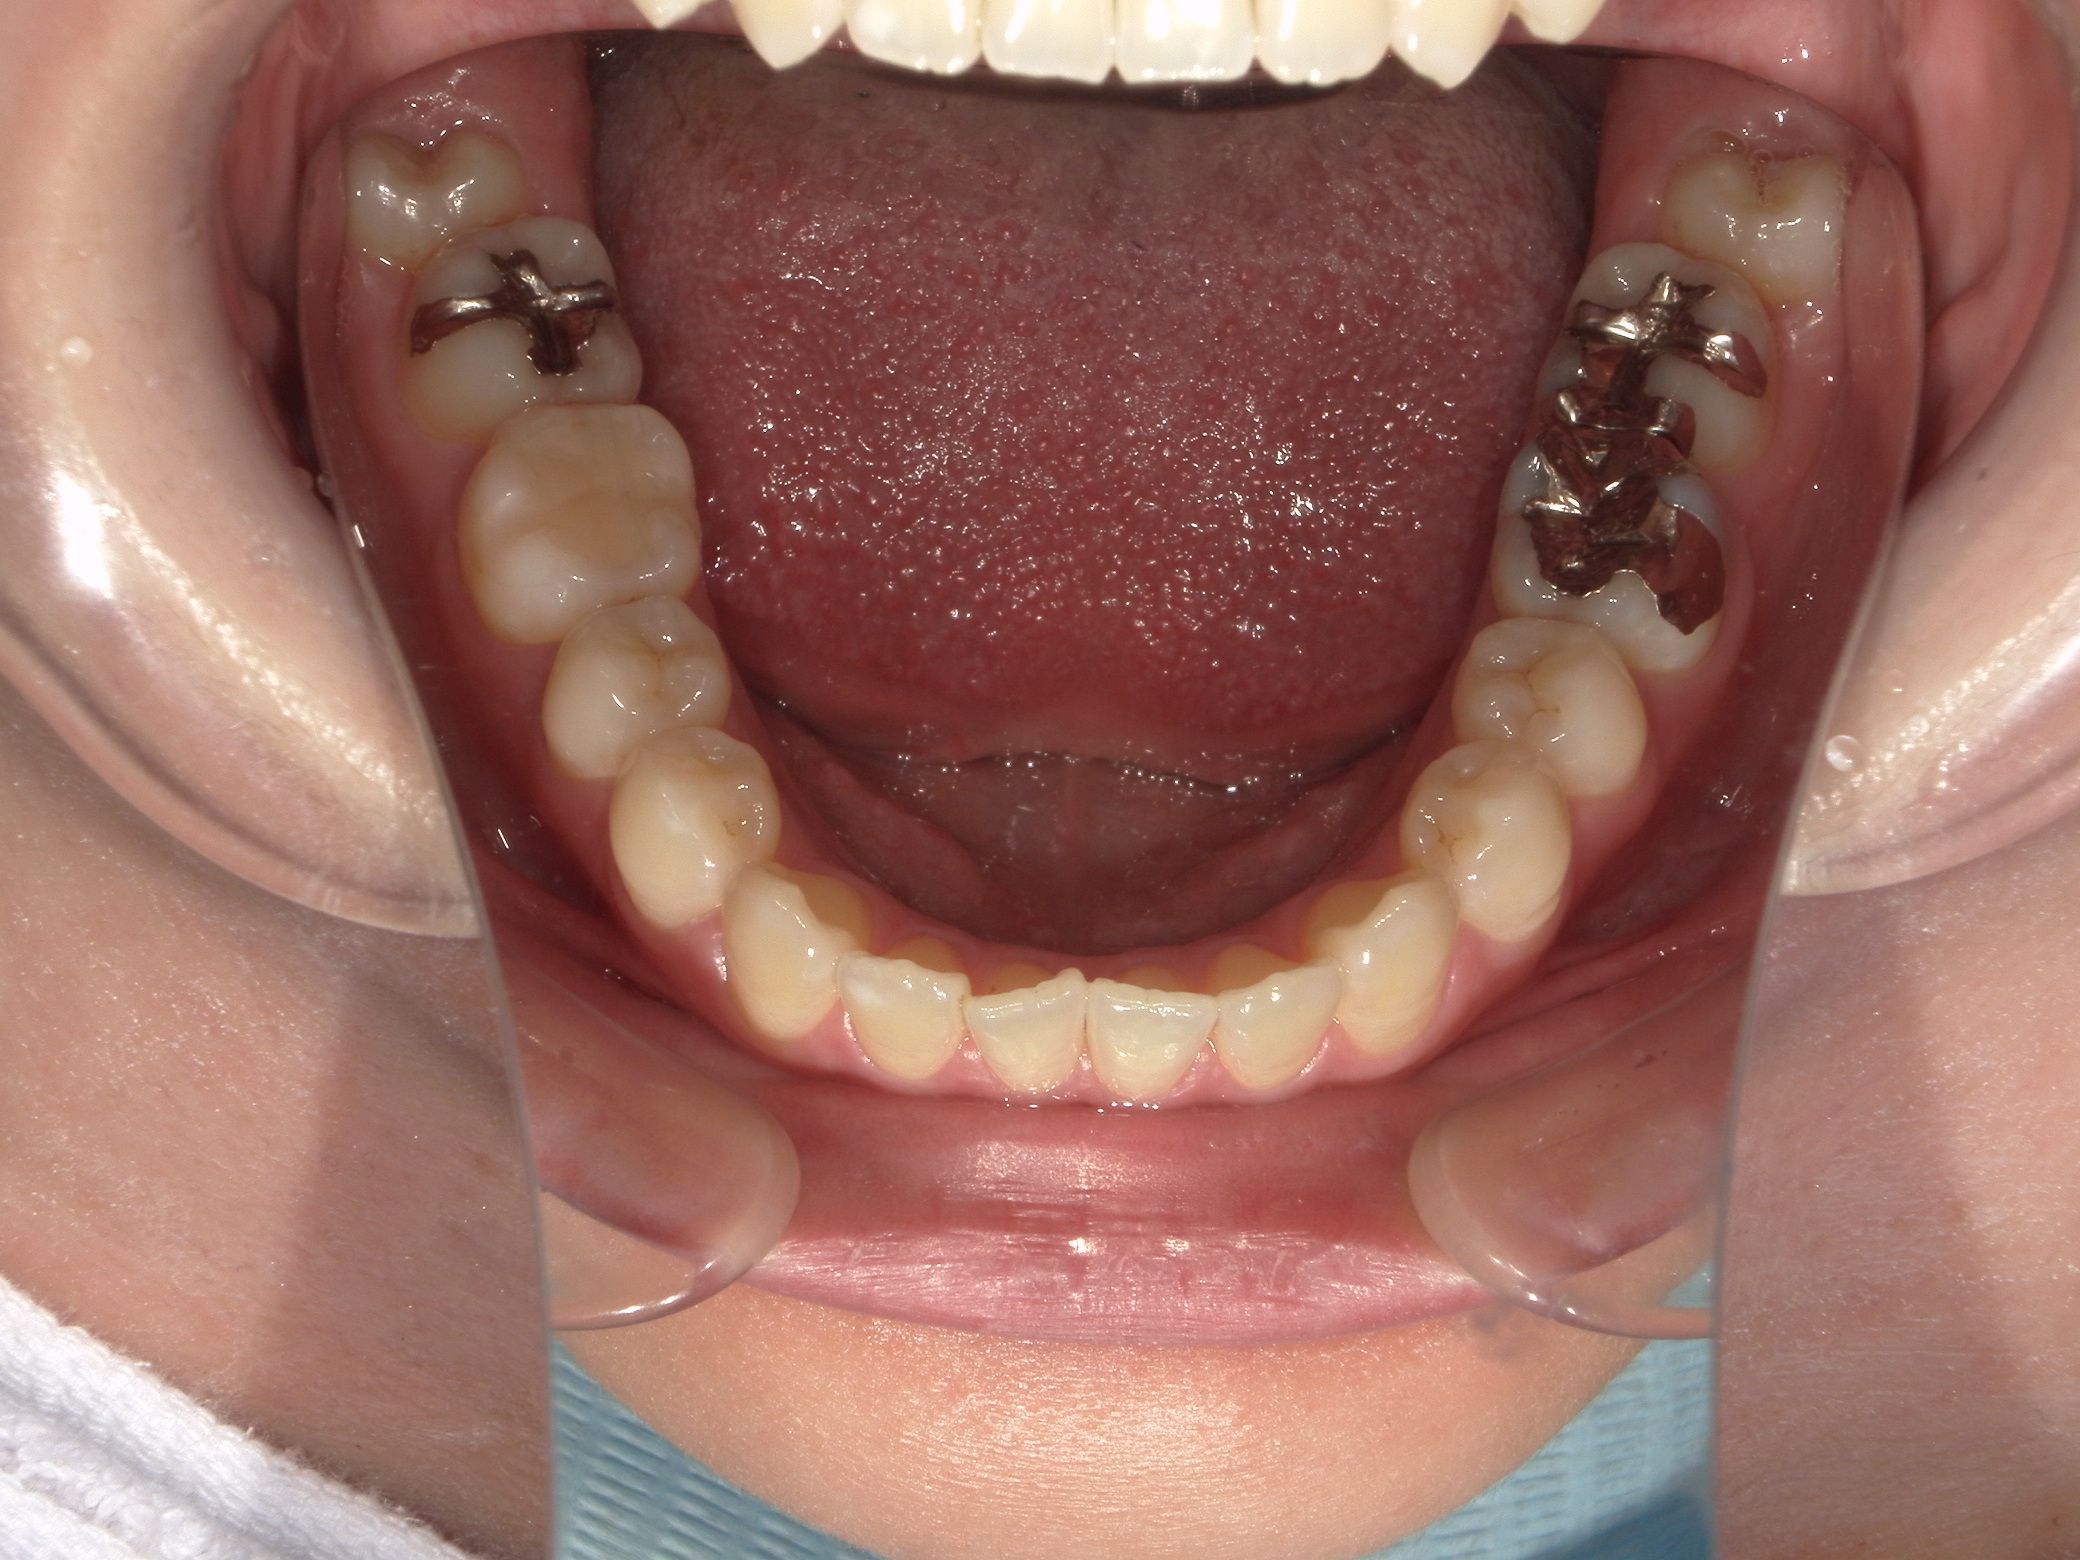

口元の突出を主訴に来院。

上下小臼歯抜歯により突出感を改善する計画を立てた。確立した咬合を崩さないように治療を進める事を目標とした。

患者はハーフリンガル矯正を希望した。

治療後、口元の突出感の改善、咬合関係は維持することができた。